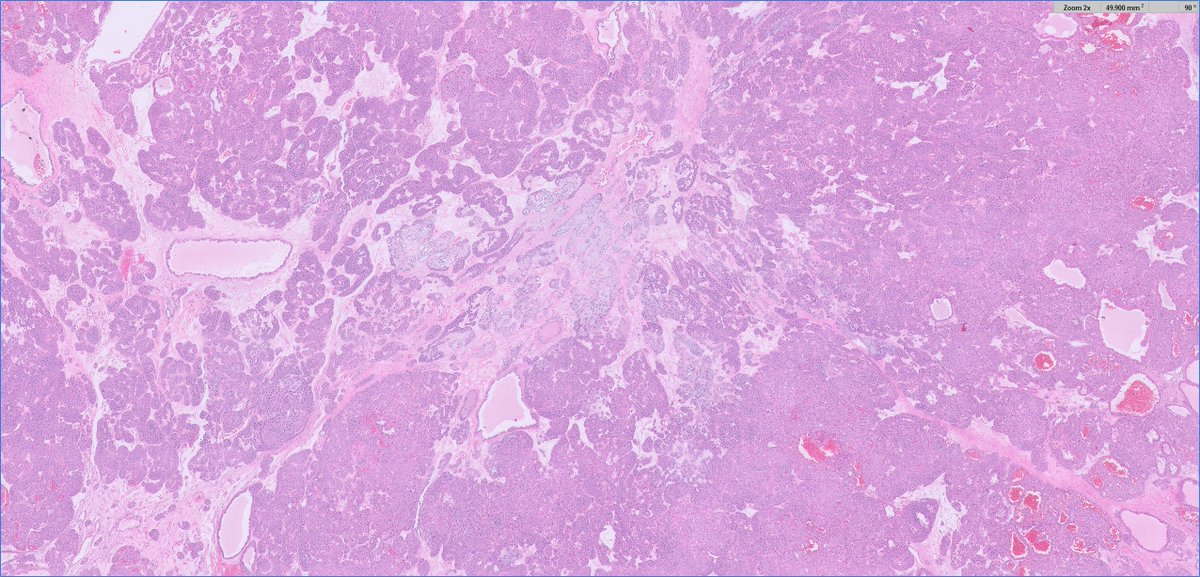

4 years

1/7 #GIpath 6th decade female. Very unusual case. Sigmoidectomy + Liver nodule excision. Dx: Neuroendocrine carcinoma with squamous differentiation vs. poorly differentiated colonic carcinoma with neuroendocrine and squamous differenitation!

9

65

141